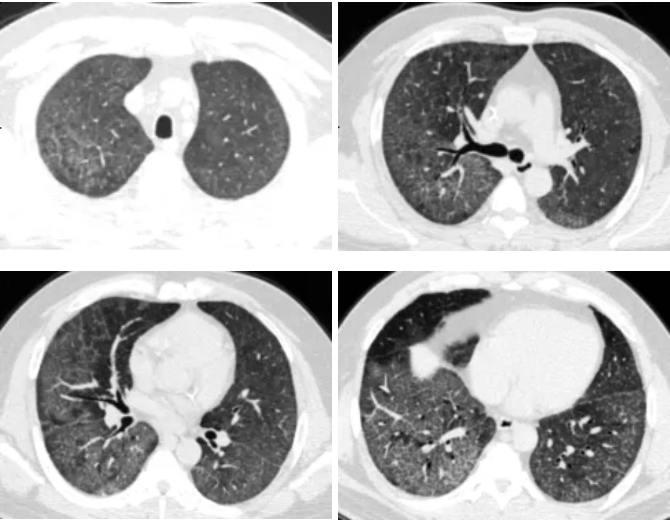

接诊后,呼吸与危重症医学科冯永海团队对孟师傅的胸部CT进行了细致分析,发现双肺弥漫性改变,高度怀疑肺泡蛋白沉积症。

QQ截图20260326083313

▲ 灌洗前胸部CT

QQ截图20260326083350

▲ 灌洗后胸部CT